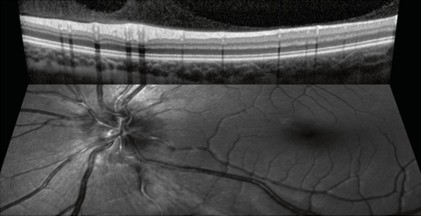

Das konfokale Laser-Ophthalmoskop (cSLO) SPECTRALIS® ist eine innovative Technologie zur Bildgebung der Netzhaut und anderer Augenstrukturen. Durch die Kombination der Selektivität von Laserlicht mit der punktgenauen Auflösung des konfokalen Scannings liefert das cSLO Bilddetails und eine Bildschärfe, die mit Fundusfotografie nicht erreicht werden können. Die cSLO-Technologie ermöglicht nicht nur die Dokumentation klinischer Befunde, sondern hebt oft auch wichtige diagnostische Details hervor, die bei der herkömmlichen klinischen Ophthalmoskopie nicht sichtbar sind. Da die cSLO-Bildgebung die Auswirkungen von Lichtstreuung minimiert, kann sie auch bei Patienten mit Medienopazitäten oder kleinen Pupillen effektiv eingesetzt werden.